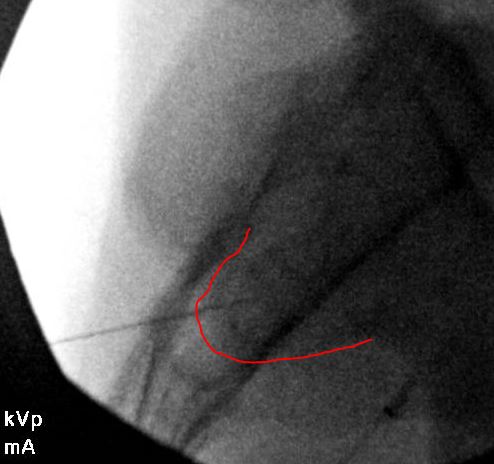

This is on the right side - not a true AP. The fluorscope is tilted caudad (with reference to the detector, not the source) and contra-lateral. The caudad tilt brings the Posterior Superior Iliac Spine (PSIS) to (about) mid joint. Then, rotate contralateral (towards midline) until the two joint lines cross just under the PSIS. This will usually give a flashlight sign - meaning, you get a small square that lights up. This is your spot. It is extremely rare that if you line it up as such, that the needle doesn't slide in the joint.

The red line highlights the PSIS. The blue lines highlight the two joint lines as they cross right below the PSIS.

The lateral in this injection is not as far anterior as I would have liked to go. However, as mentioned above, doing these under CT has given me a much great appreciated for how these joint edges are - and sometimes, there is no way you can go further because of the jagged edges.